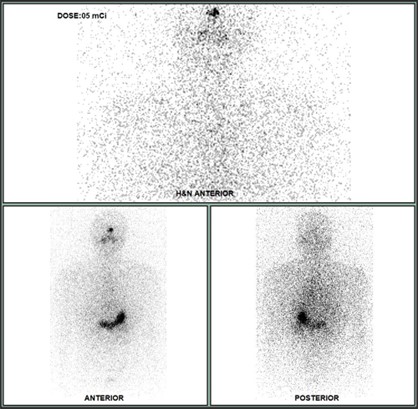

Xạ hình tuyến giáp với I-131 (liều 2 mCi):

Hình 2: Hình ảnh tăng hoạt tính phóng xạ khu trú tại vùng cổ và di căn lan tỏa hai phổi (mũi tên đỏ)